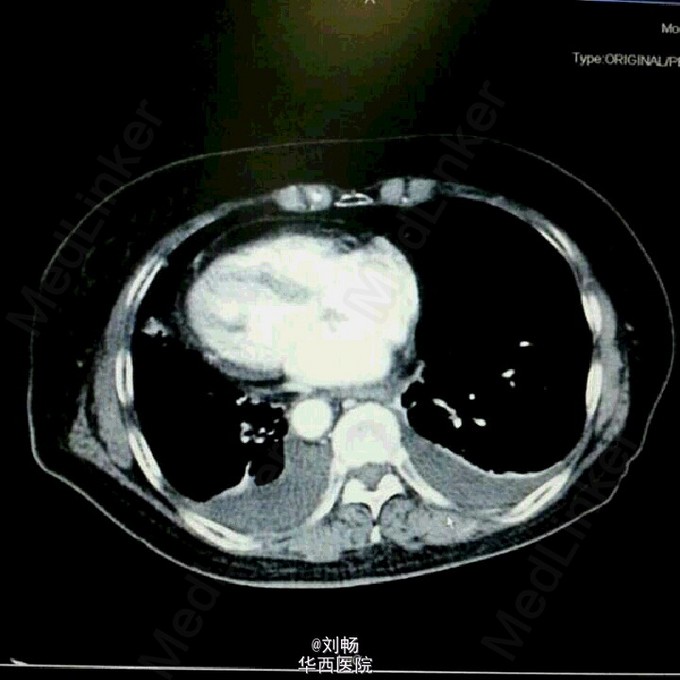

遭遇镜像人!

“镜像人”,学名:全脏器反位。患者老年女性,自发性腹痛3天,入院考虑自发性脾破裂,全脏器反位。术中证实脾动脉瘤,脾破裂。术中照片也秀一下。记住:你的心脏在左边,他的心脏在右边,当他摸着右边胸口对你发誓的时候,并不是在忽悠你哦。

“镜像人”,学名:全脏器反位。患者老年女性,自发性腹痛3天,入院考虑自发性脾破裂,全脏器反位。术中证实脾动脉瘤,脾破裂。术中照片也秀一下。记住:你的心脏在左边,他的心脏在右边,当他摸着右边胸口对你发誓的时候,并不是在忽悠你哦。